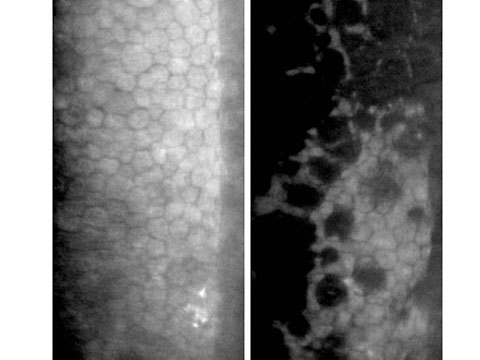

此外,手術前亦建議進行角膜內皮細胞掃瞄,由於角膜內皮是維持角膜清晰的重要組織,內皮細胞亦沒有新增復原能力,如術前發覺出現細胞數量不足或退化情況,進行白內障手術時必須加倍小心,以盡量減少內皮細胞流失,及出現術後持續性角膜水腫的機會。

正常角膜內皮細胞 (左圖) ; 不正常退化內皮細胞(右圖)